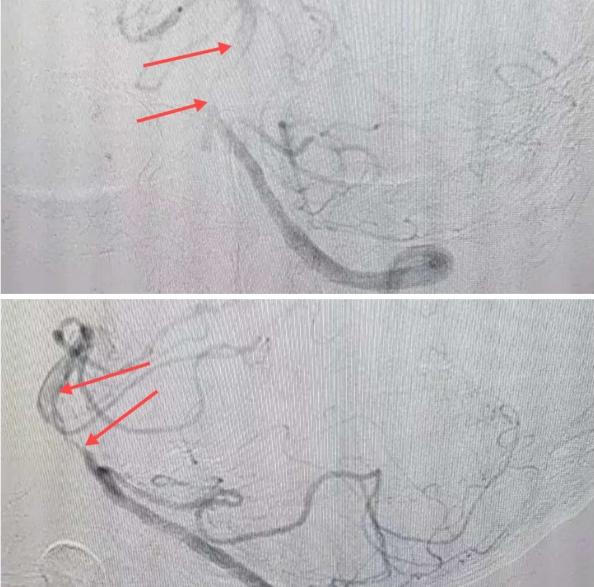

在經(jīng)造影后,主刀醫(yī)生腦一科副主任楊慶堂發(fā)現(xiàn)患者基底動(dòng)脈下段重度狹窄且狹窄段以遠(yuǎn)有大負(fù)荷血栓,其狹窄處考慮為動(dòng)脈夾層,手術(shù)難度及風(fēng)險(xiǎn)較大。楊慶堂副主任在彭壯副主任醫(yī)師的協(xié)助下運(yùn)用spaceman(太空人)技術(shù),中間導(dǎo)管抵近血栓抽吸配合支架拉栓,成功開通血管。再次造影可見基底動(dòng)脈管腔明顯增寬,遠(yuǎn)端血管顯影良好,且等待20分鐘后造影仍顯示血流通暢。楊慶堂副主任考慮到本次手術(shù)時(shí)間不宜過長,現(xiàn)患者基底動(dòng)脈及分支前向血流維持良好,給予其抗栓藥物應(yīng)用后結(jié)束手術(shù),并建議患者3個(gè)月后復(fù)查造影,明確其基底動(dòng)脈夾層情況。

造影可見血管夾層和大量血栓形成